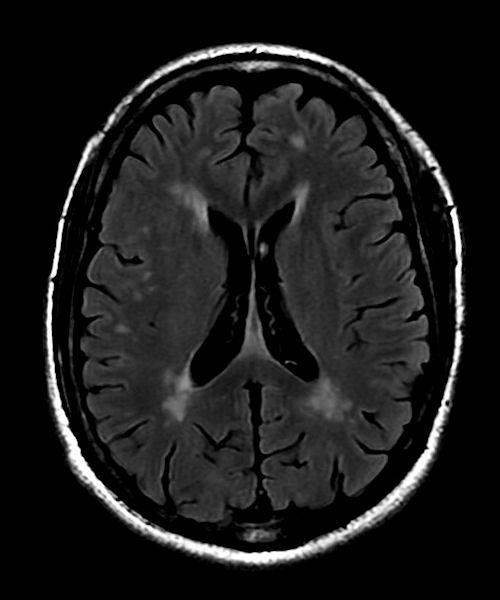

Diffuse deep white matter lesions are not characteristic for MS.